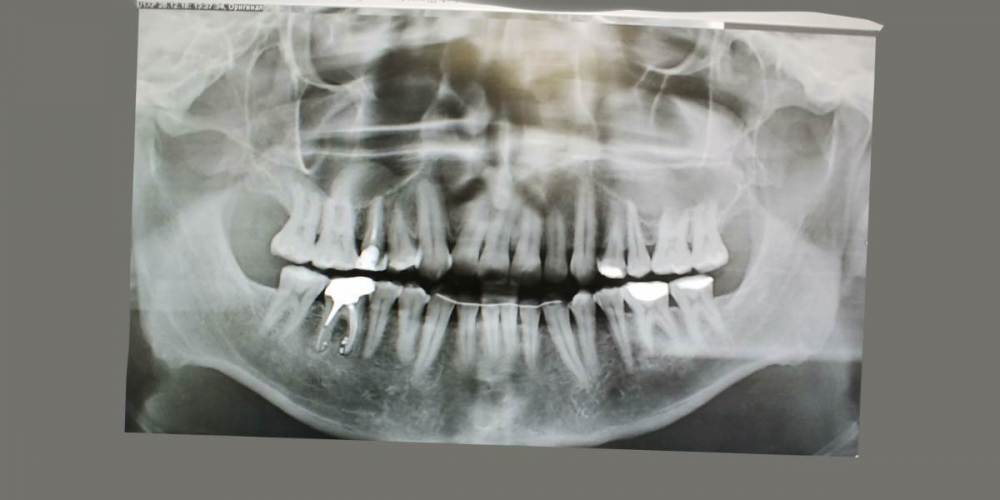

kamacho Опубликовано 15 февраля, 2024 Поделиться Опубликовано 15 февраля, 2024 Уважаемые специалисты. Беспокоит 15 зуб Коронка стоит 2-4 года. Беспокоит переодическая кровь при чистке флосом и иногда неприятный запах между 16 и 15 зубом (как правило ближе к 15ому) Иногда теряю обоняние. Обильный серый налет на языке по утрам. После ирригатора, флоса и тщательной чистки обоняние возращается. В клинике сказали что коронка прилегает хорошо и выступов нету(посещал дважды). Если будет возможность дополню тему прицельными снимками. 1)Скажите пожалуйста, есть ли показания для лечения этого зубика? 2)Могут ли не до конца пролеченные корни вызывать такую симптоматику ? 3)И если да то что лучше сделать? Стоит ли заменить на имплант ? Так же буду очень признателен если кто-то предложит специалиста Москве к которому можно было бы обратиться. Немножко предыстории и описание кт если вам интересно. Корни пломбировали где-то лет 10-15 назад. Сначала закрывали пломбой, которая потемнела. Обратился по поводу эстетики в клинику, терапевт хотела перелечить каналы, но когда сняла пломбу увидела цемент и сказала что не получится. Предложили закрыть коронкой и не трогать. С тех пор обращатся в клиннику дважды с жалобами про кровь и трудность гегиены. Предлагали акуратней пользоватся нитью и чаще следить за гегиеной. 1.5 зуб — депульпирован. Коронковая часть: восстановлена искусственной коронкой. Вариант строения: два корня, два канала. Обтурация: ЩК - установлен штифт на 1⁄2 длины корня, далее канал обтурирован пломбировочным материалом, не доходя до верхушки корня на 2,4 мм. НК - установлен штифт на 1⁄2 длины корня, далее канал обтурирован пломбировочным материалом, не доходя до верхушки корня на 2,9 мм. Периодонтальное пространство: не изменено. Пародонт: без особенностей. Ссылка на комментарий

kamacho Опубликовано 24 февраля, 2024 Автор Поделиться Опубликовано 24 февраля, 2024 (изменено) Так же приложу документ-опись риентгенолога по всем зубками с изображениями. снимок был сделан в 22 году. Наврятли кто-либо захочет перечитывать такое количество информации ради развлечения. Но для истории добавлю. Изменено 24 февраля, 2024 пользователем kamacho Ссылка на комментарий